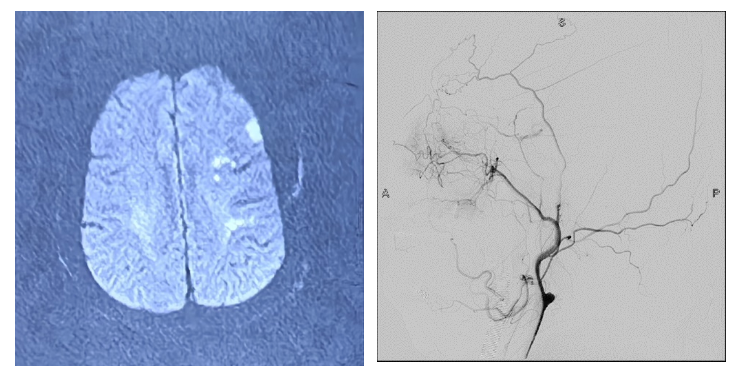

術前造影